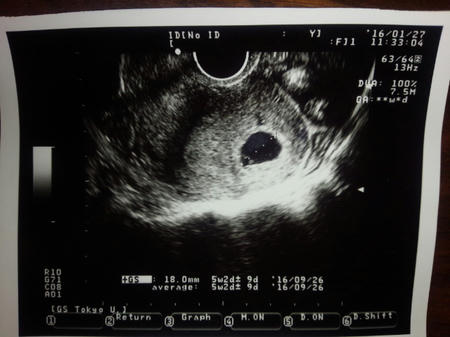

妊娠したのは素直に嬉しいとは思うし、驚いてはいるけれども

まだまだ全く実感がわいていません。

今も腹の中に一人の人間が出来上がりつつあるのが、判りません。

ツワリでだんだんと認識ができるとは言うけれども

ここまで予兆っぽいのはあるのだけれども、次の検診まで不安は長いです

実際妊娠初期の流産の確率は10%超え。

1割か。